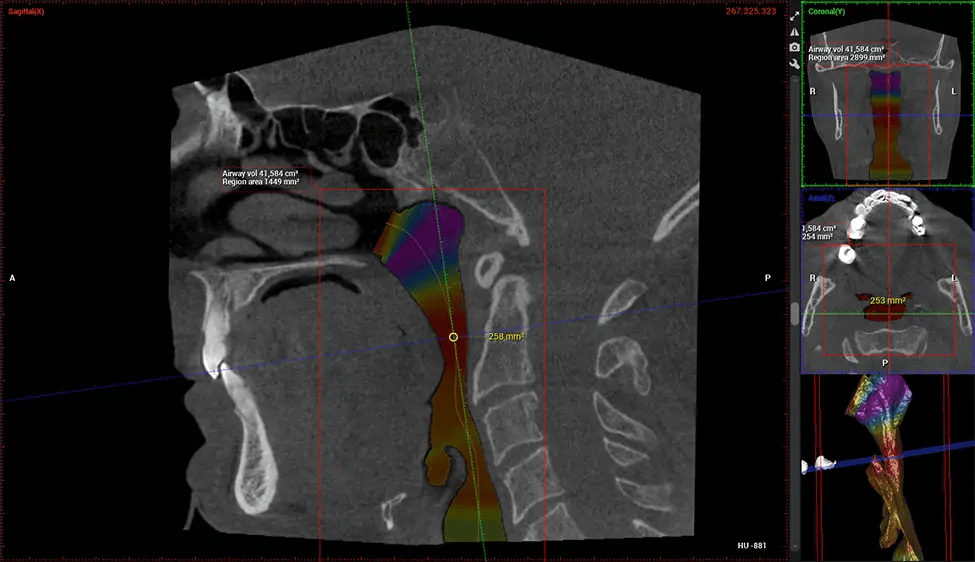

After the scanning process, the captured X-ray images are processed by the CBCT software, which applies algorithms to reconstruct a detailed 3D image of the scanned area. The software compiles these individual X-ray images and creates a digital 3D representation of the patient’s anatomy. The reconstructed 3D CBCT image can be viewed and analyzed by the dentist or radiologist. This image can be manipulated, rotated, and zoomed in or out to examine specific structures and evaluate the patient’s condition.